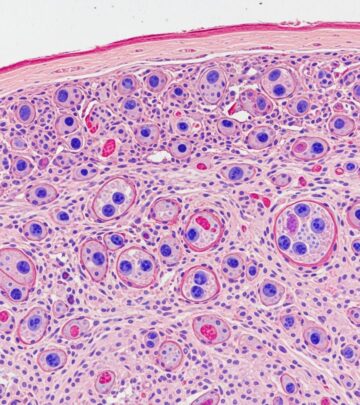

Fibrofolliculomas in Birt-Hogg-Dubé Syndrome Images